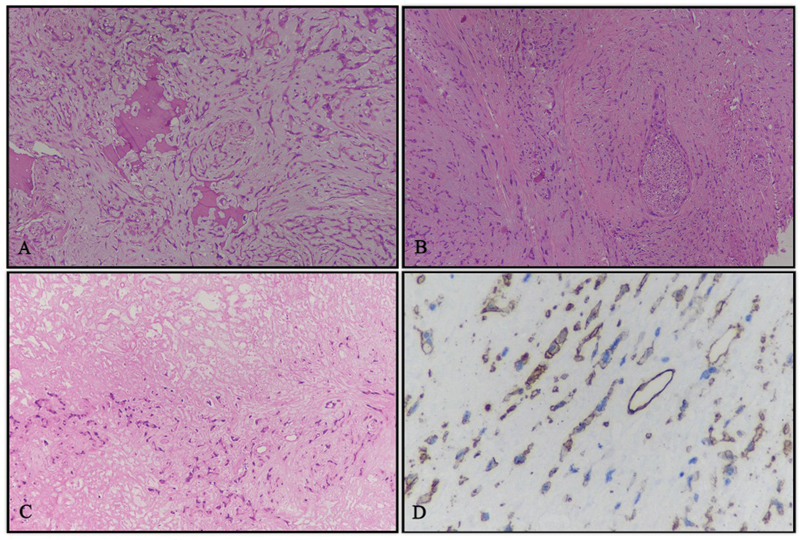

A 56-year-old lady, with no comorbidities and no habits presented with right submandibular swelling which gradually increased over 2 years. On clinical examination, the submandibular mass was lobulated and soft in consistency measuring 3 × 4 cm and not fixed to the overlying skin. There were no signs of inflammation and the swelling was not tender to touch. There was a palpable left level Ib neck node of 1.5 × 2 cm in size in the contralateral neck. The rest of the head and neck area examination was noncontributory. Computed tomography (CT) imaging ([Fig. 1A]) done was suggestive of a 28 × 27 × 39 mm sized ill-defined soft tissue lesion seen in the hemimandible along the right lower alveolus which was causing destructive cortical erosion. The adjacent enhancing soft tissue component showed loss of fat planes with the right submandibular gland inferiorly. A peripherally enhancing centrally necrotic left submandibular lymphadenopathy was present measuring 18 × 17 mm in size. Whole-body positron emission tomography-CT (PET-CT) scan done was suggestive of 3 × 2.4 cm sized fluorodeoxyglucose (FDG) avid spiculated lesion in the right submandibular region, eroding overlying angle and adjacent posterior body of the right hemimandible and infiltrating the right anterior belly of the digastric and closely abutting platysma. A 1.7 × 2.2 cm sized FDG avid left cervical level Ib lymph node was also noted. Heterogeneously, FDG avid discrete cervical level Ia and bilateral level II lymph nodes were also present. Mild FDG avid multiple subpleural and parenchymal nodules were noted in bilateral lung fields suggestive of metastasis ([Fig. 1C]). Biopsy from the right submandibular region was suggestive of EHE. In view of rare disease and asymptomatic suspicious lung metastasis, the case was discussed in a multidisciplinary tumor board following which the patient was taken up for wide local excision with right segmental mandibulectomy with bilateral supraomohyoid neck dissection. Histopathology of the resected specimen was suggestive of EHE involving the right submandibular gland and underlying bone ([Fig. 2A]) with maximum tumor size of 2.8 cm, medial and lateral soft tissue margins were involved by the tumor, perineural invasion was present ([Fig. 2B]), and lymphovascular invasion was not seen. Federation Nationale des Centres de Lutte Contre Le Cancer (FNCLCC) grade 4, mitotic rate was < 1/50 high-power field (HPF), and necrosis 10%. ([Fig. 2C]). One lymph node in the left level Ib was positive (out of 5), while the right-sided nodes were negative. Tumor cells were immunoreactive for CD34 ([Fig. 2D]). In view of positive margin and lymph node involvement, the patient was planned for adjuvant radiation to a dose of 60 Gy in 30 fractions to postoperative bed and involved the lymph node region by image-guided external beam radiotherapy (RT) technique. In phase 1, 50 Gy in 25 fractions was delivered to the tumor bed and bilateral neck region, and in phase 2 (boost), 10 Gy in 5 fractions was delivered to the tumor bed and involved the nodal region, Therefore, a total of 60 Gy in 30 fractions, 2 Gy per fraction, one fraction daily, over 6 weeks along with cisplatin chemotherapy (40 mg/m2) concurrently was given once a week, which she tolerated well with grade 1 dermatitis and grade 2 mucositis. The patient recovered from acute toxicities 2 weeks after completion of RT and was started on targeted therapy tablet pazopanib (dose 400 mg) twice a day to control systemic disease and reduce the risk of locoregional failure. PET-CT scan repeated after 3 months was suggestive of postoperative fibrosis of the right submandibular region with stable pulmonary metastasis. At 2-year follow-up, the patient is asymptomatic and on tablet pazopanib dose reduced to 200 mg twice a day due to oral mucositis. Latest PET-CT showed local-regional control and metabolically inactive pulmonary metastatic diseases.

Fig 2 : Histopathological findings. (A) Cords of cells infiltrating and destroying bone and embedded in a myxohyaline matrix, hematoxylin and eosin (H&E) stain, 10 × . (B) Perineural invasion, H&E stain, 10 × . (C) Partly viable tumor and partly coagulative necrosis (in the upper half of image), H&E stain, 10 × . (D) Immunohistochemistry for CD34, showing positivity for tumor cells and interspersed vessels within the tumor, DAB-H, 10 × . H&E, hematoxylin and eosin stain; DAB-H, diaminobenzidine-hematoxylin.